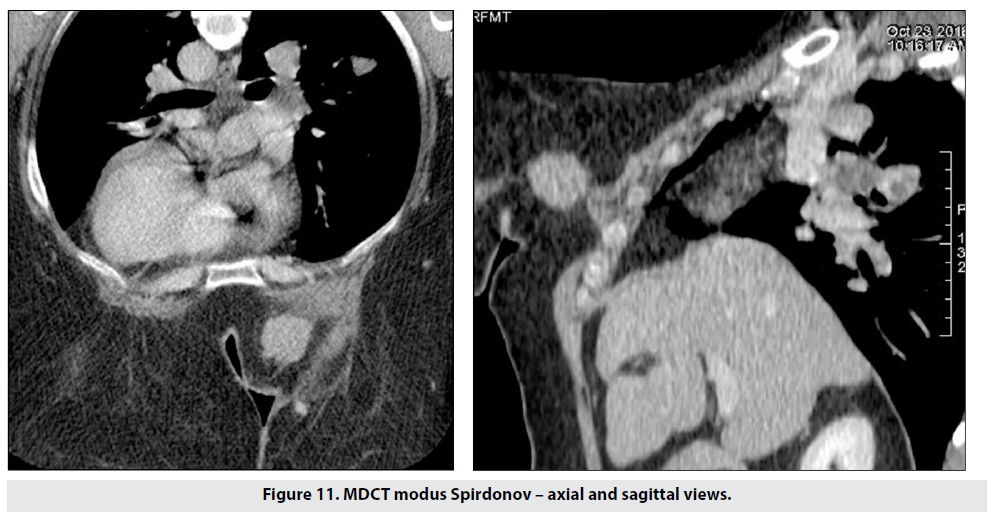

Figure 11 shows the capabilites of the method for detecting chest wall invasion and pulmonary spread simultaneously. This patient was contraindicated for MRI due to breast size and severe thoracic kyphosis.